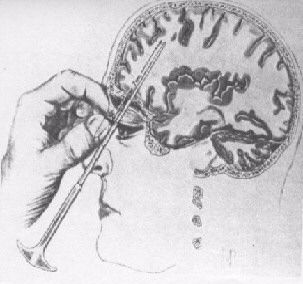

ロボトミー

1935年、ジョン・フルトン(John

Fulton)とカーライル・ヤコブセン(Carlyle

Jacobsen)がチンパンジーにおいて前頭葉切断を行ったところ、性格が穏やかになったと報告したのを受け、同年、ポルトガルの神経科医エガス・モニスがリスボンのサンタマルタ病院で外科医のペドロ・アルメイダ・リマ(Pedro

Almeida

Lima)と組んで、初めてヒトにおいて前頭葉切裁術(前頭葉を脳のその他の部分から切り離す手術)を行った。その後、1936年9月14日ワシントンDCのジョージ・ワシントン大学でも、ウォルター・フリーマン

(Walter Jackson Freeman II)

博士の手によって、米国で初めてのロボトミー手術が激越性うつ病患者(63歳の女性)におこなわれた。当時に於いて治療が不可能と思われた精神的疾病が外科的手術である程度は抑制できるという結果は注目に値するものであって世界各地で追試され、成功例も含まれたものの、特にうつ病の患者の6%は手術から生還することはなかった。また生還したとしても、しばしばてんかん発作、人格変化、無気力、抑制の欠如、衝動性などの重大かつ不可逆的な副作用が起こっていた。